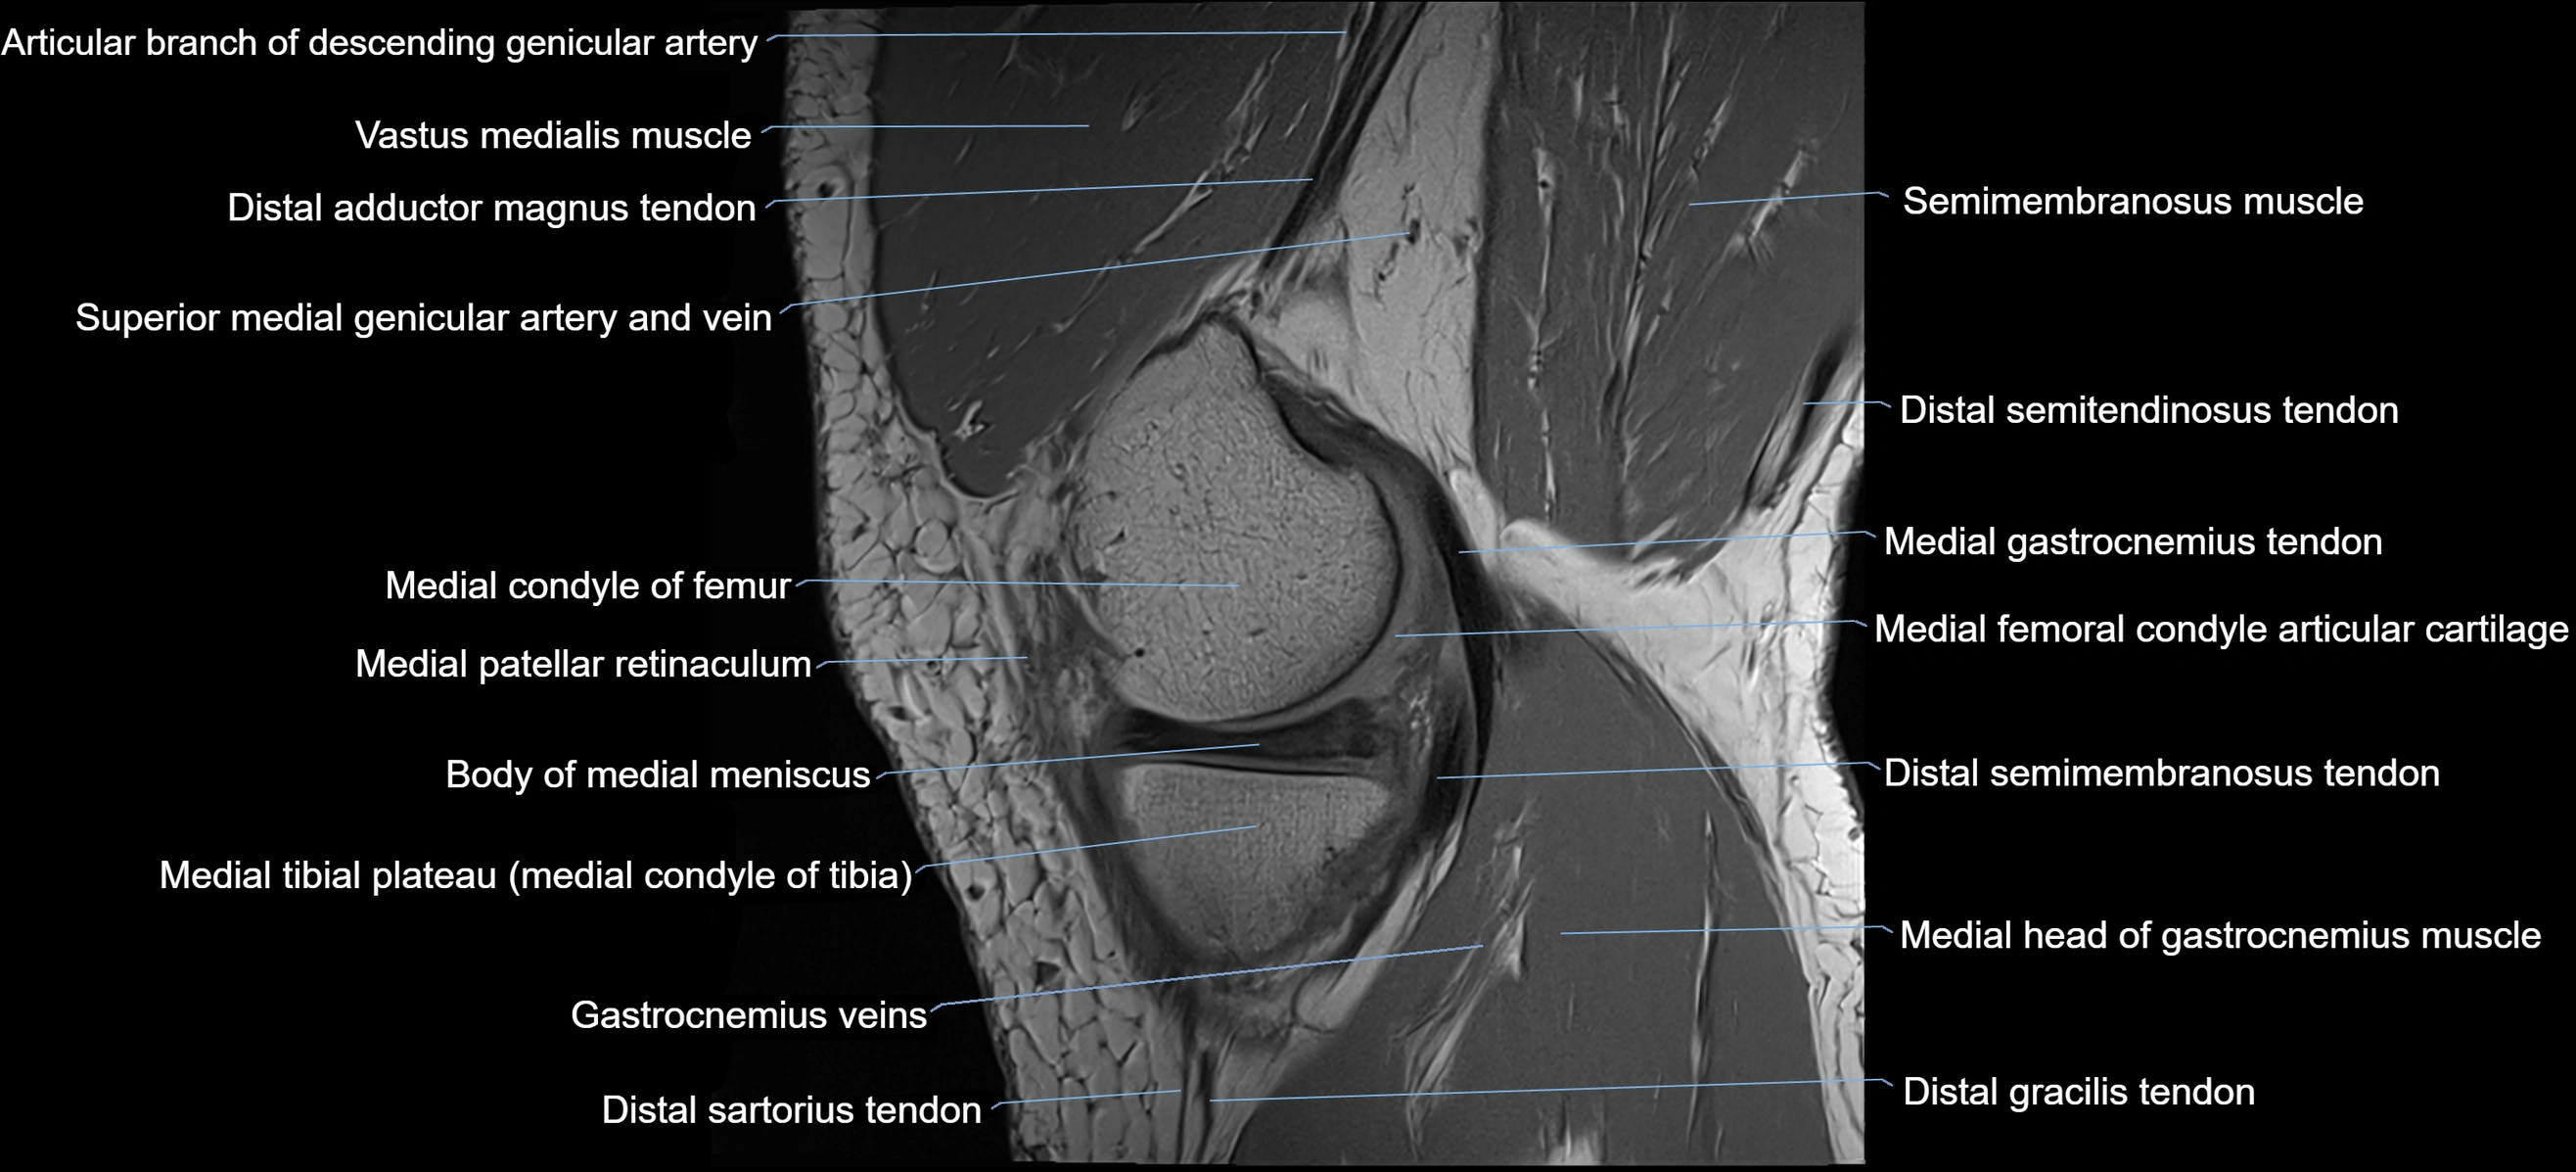

- Body of medial meniscus

- Medial condyle of femur

- Medial gastrocnemius tendon

- Medial head of gastrocnemius muscle

- Medial patellar retinaculum

- Medial tibial plateau